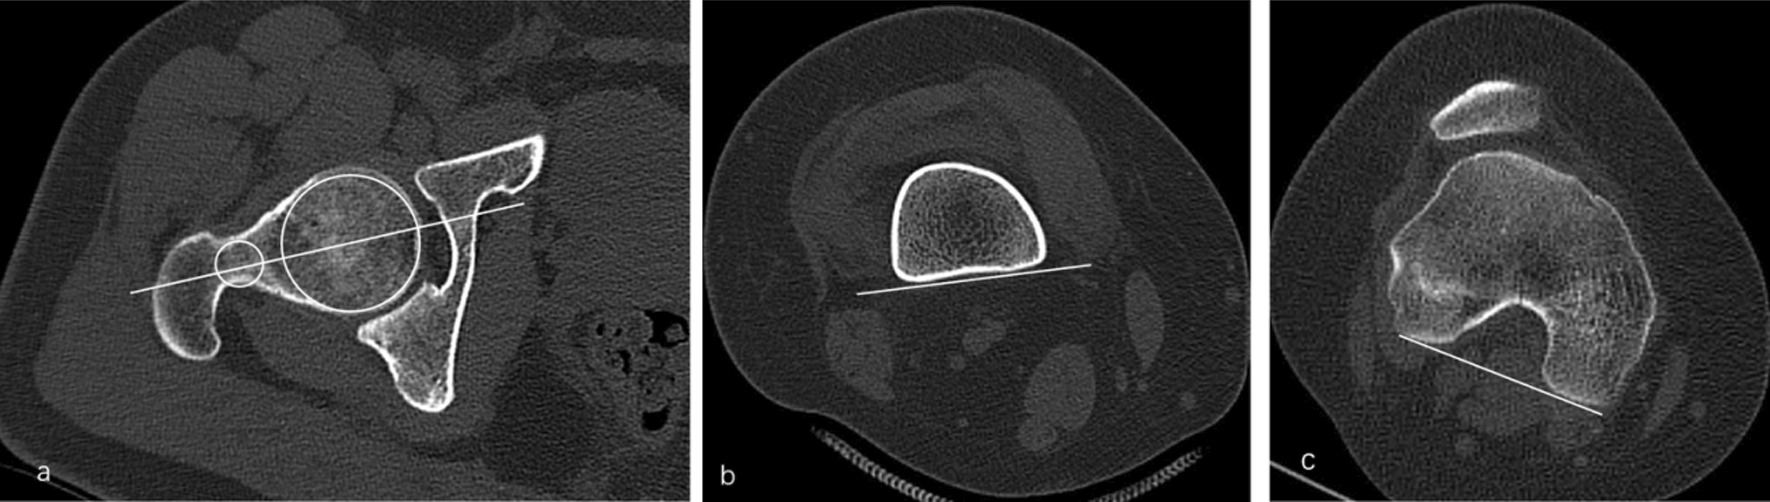

Three lines were drawn to evaluate the femoral torsion in CT images. The first line passes through the center of the femoral head and neck (FNA, Fig. 1a). The second line is the tangent line to the gastrocnemius muscle in the posterior compartment of the leg (DFL, Fig. 1b) and the third line is the tangent line to the posterior condyles (PCL, Fig. 1c). The angle between FNA and PCL (femoral anteversion angle, FAA) and the angle between DFL and PCL (distal femoral torsion, DFA) were measured.

Fig. 1.

Three lines were drawn to evaluate the femoral torsion in CT images. The first line passes through the center of the femoral head and neck. (FNA, a). The second line is the tangent line to the gastrocnemius muscle in the posterior compartment of the leg (DFL, b). The third line is the tangent line to the posterior condyles (PCL, c). The angle between FNA and PCL (femoral anteversion)and the angle between DFL and PCL (distal femoral torsion) were measured.